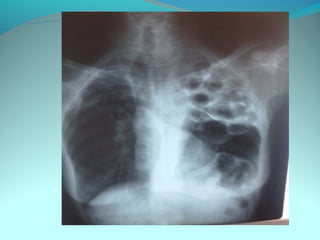

Opacité heterogene de tout le P.G peu dense et siege de clarté

arrondie de taille variable dont la plus volumineuse est sous

claviculaire et axillaire arrondie de 4cm de diam a paroi de 2mm

d’epaisseur

DIAGNOSTIC:

Tuberculose pulmonaire gauche étendu cavitaire